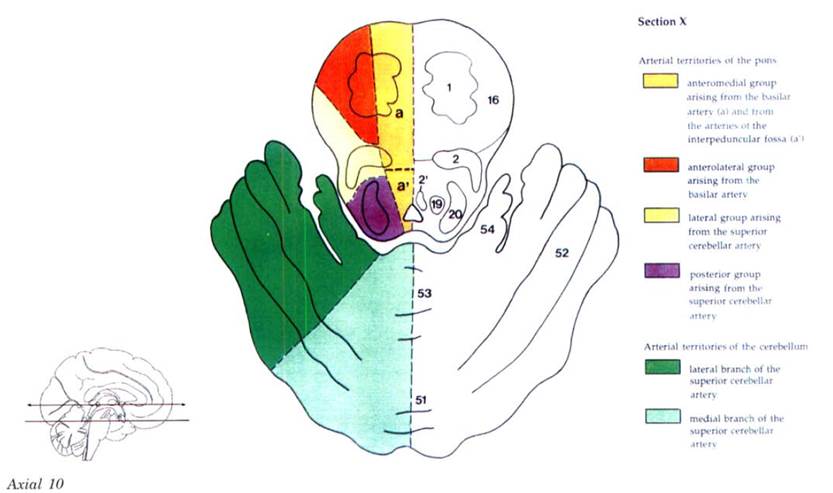

Cerebral vascular territories

Brainstem